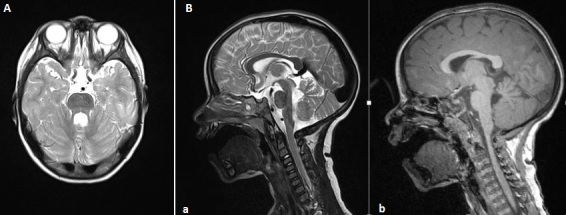

Din punct de vedere imagistic, poate fi indicată efectuarea unui RMN cerebral care evidențiază „semnul de dinte molar” pe RMN: testul imagistic va arăta că vermisul cerebelos este absent și că trunchiul cerebral este atipic dezvoltat, acest aspect semanand cu un dinte; aceasta se evidențiază printr-un model care seamănă cu un dinte.